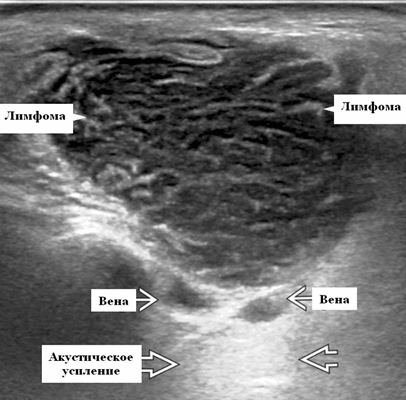

Околоушная неходжкинская лимфома на УЗИ

- Узловая неходжкинская лимфома (НХЛ): одиночные или множественные увеличенные яйцевидные внутрипаротидные лимфатические узлы, которые на УЗИ гомогенно гипоэхогенны по отношению к паренхиме околоушной железы, эхо-картина сетчатая. Заднее акустическое усиление. Выраженная внутриузловая гиперваскуляризация

Лучший диагностический признак на УЗИ при узловой НХЛ: множественные однородные, четко выраженные образования околоушных желез и лимфаденопатия верхних отделов шеи. Паренхиматозная НХЛ: инфильтративная околоушная опухоль, фон СШ, BLEL

Серошкальное УЗИ. Узловая НХЛ. Одиночные или множественные увеличенные яйцевидные внутрипаротидные лимфатические узлы. Гомогенно гипоэхогенный по отношению к паренхиме околоушной железы. Сетчатый эхосигнал. Заднее акустическое усиление. Первичная паренхиматозная НХЛ. Рассеянный, неоднородный эхосигнал; нечеткие, гипоэхогенные, похожие на опухоль участки. В пунктате внутрикистозная или паренхиматозная кальцификация из-за конечной стадии воспалительного изменения. Небольшие кистозные области образуются из-за сдавления терминальных протоков лимфоидной гипертрофией. Множественные небольшие гипоэхогенные участки (представляют собой лимфоидные агрегаты), разбросанные на фоне ткани слюнной железы. Изменения могут имитировать хронический сиалоаденит и диагноз часто ставится при биопсии. На УЗИ необходимо искать аналогичное поражение других слюнных и слезных желез, фон синдром Шегрена, BLEL. Может иметь или не иметь перипаротидную и шейную лимфаденопатию